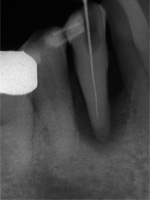

Patient(64):

Dieser Zahn wurde schon geraume Zeit zuvor von einer Kollegin im Notdienst eröffnet und anschlies­send mit einer aufwendigen Amal­gamrestauration ästhetisch an­sprechend wieder verschlossen. (Bild 1) Uns blieb noch WK/WF, was bei massiver Überstopfung der hin­teren Wurzel auch gelang (Bild 2).

"Überstopfen ist immer noch besser als Unterstopfen" laut Koçkapan. OK, hier wurde des Guten aber ganz eindeutig zuviel getan.

Also direkt neben dem Zahn das Zahnfleisch ein wenig angehoben und zur Seite gedrängt und dann mit einem scharfen Löffel den Überschuss vollständig entfernt.

Schon 8 Monate später ist eine deutliche Verbesserung der Gesamt­situation unverkennbar (Bild 3). Verlorengegangene Knochensubstanz wurde in Teilen schon wieder aufge­baut, doch ist noch gar nichts entschieden. Schaun mer also ma'.

Abrechnungstechnisch hat der Mut zur WR an 38 gefehlt, deshalb nur EXZ1.